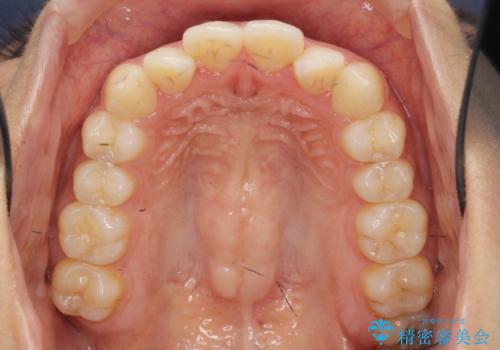

- 前歯のガタつき、上下たがい違いになっている歯並び(クロスバイト)の改善を求めて来院されました。

インビザラインによる矯正治療を行いますが、クロスバイトの改善をワイヤー部分矯正で事前に行うことにより治療期間の短縮する治療計画を立案します。

上下すれ違った噛み合わせはマウスピースでは改善に時間がかかり、またねじれが残ってしまうことも多々見られます。

マウスピース矯正を行う前に、これらの症状の改善の得意なワイヤー部分矯正を行うことで治療期間を短縮し、確実にすれ違いを改善することができます。